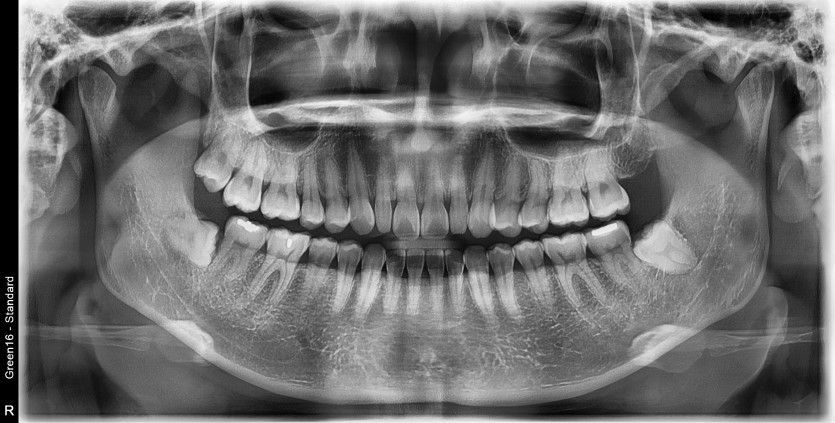

#18,38,48 사랑니 발치

구강 외과 전문의가 당일 발치했습니다.